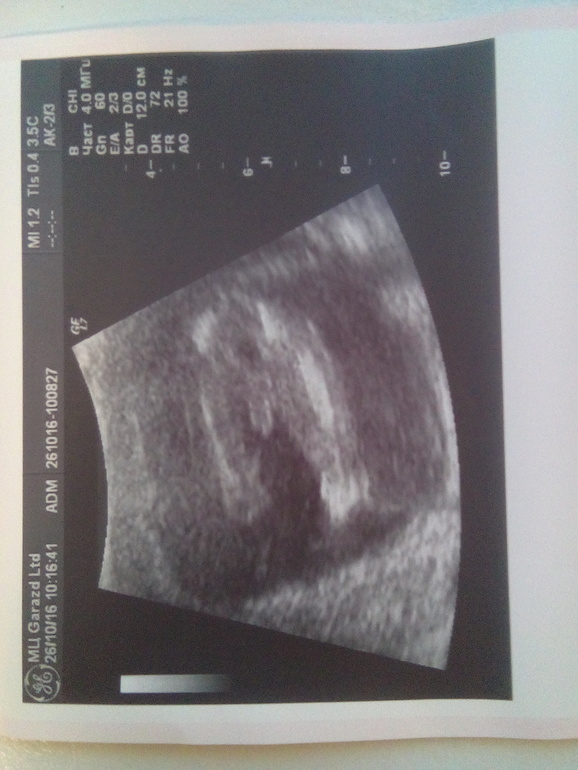

В целом Узи мне понравилось все рассказали показали нафоткали)Соответствует сроку 17 недель все у нас хорошо только тонус ,но я его не чувствую,ну и однократное обвитие(

И у нас будетМАЛЬЧИК)Мне конечно не верится вдруг куда то денется)

Вот и фото)Гляньте девченки действительно ли мальчик?